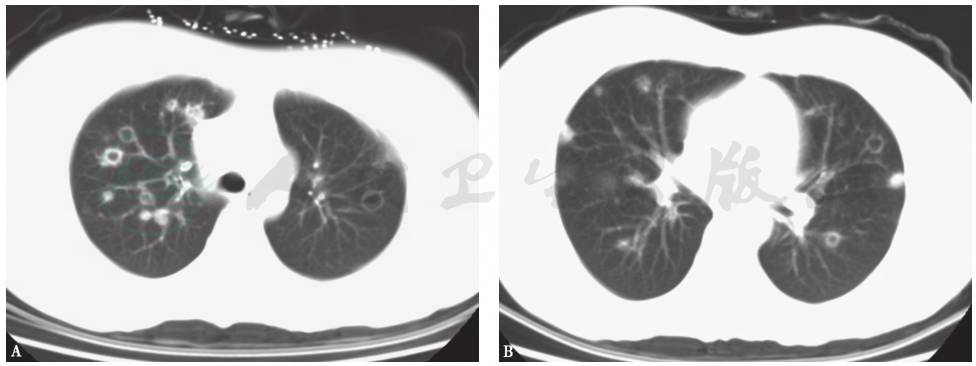

通过一系列经验的、循证的临床证据分析,患者肺内病变的性质诊断为隐源性机化性肺炎(COP),这也可解释为何经验性抗感染治疗无效。COP是一组原因不明的少见疾病。其相应的临床-放射-病理学定义为没有明确致病原(如感染)或其他临床伴随疾病(如结缔组织疾病)情况下出现的机化性肺炎,大多对糖皮质激素治疗有较好反应。COP发病率男女基本相等,发病年龄多在50~60岁,与吸烟无明显相关性。其临床表现缺乏特异性,常为亚急性起病,病程较短(中位病期<3个月),常见临床症状为发热、刺激性咳嗽、乏力,伴体重下降、厌食及胸闷等不适,咯血、夜间盗汗、气胸、纵隔气肿及关节肌肉疼痛少见,气短的症状较轻,上述临床症状可在数周内进展。体检时可发现局限性或广泛性的湿啰音和(或)Velcro啰音,多位于两肺中下部,部分患者亦可无任何体征表现。常规实验检查无特异。肺功能主要表现为轻至中度限制性通气障碍。大多数患者胸部影像学检查可有异常发现,且具有“五多一少”的特点,即多态性、多发性、多变性、多复发性、多双肺受累(图13),蜂窝肺少见。COP的主要病理变化是呼吸性细支气管及以下小气道和肺泡腔内有机化性肺炎改变,病变表现单一,时相一致,呈斑片状和支气管周围分布,位于气腔内,肺结构没有破坏。

图13 隐源性机化性肺炎胸部CT表现

女性患者,64岁,咳嗽、间断发热4个月余。胸部CT见右肺多叶段高密度实变影,右下肺膨胀不全伴轻度反晕征

另外,患者胸部CT可见多发环状高密度影,临床上常将这一改变称为“环礁征”,亦称“反晕征”。在HRCT肺窗观察可见病灶中心密度低,呈磨玻璃状,周围是新月形或环形高密度。出现这种表现是由于肺泡间隔炎性细胞浸润和细胞碎片形成病灶中心磨玻璃状密度,而肺泡管机化性肺炎或致密、均匀肺泡间细胞浸润导致周围新月形或环形高密度的致密影。